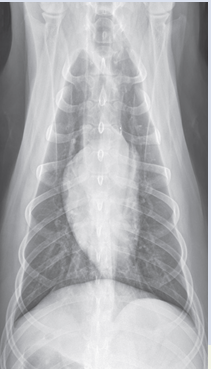

VD

inspiration